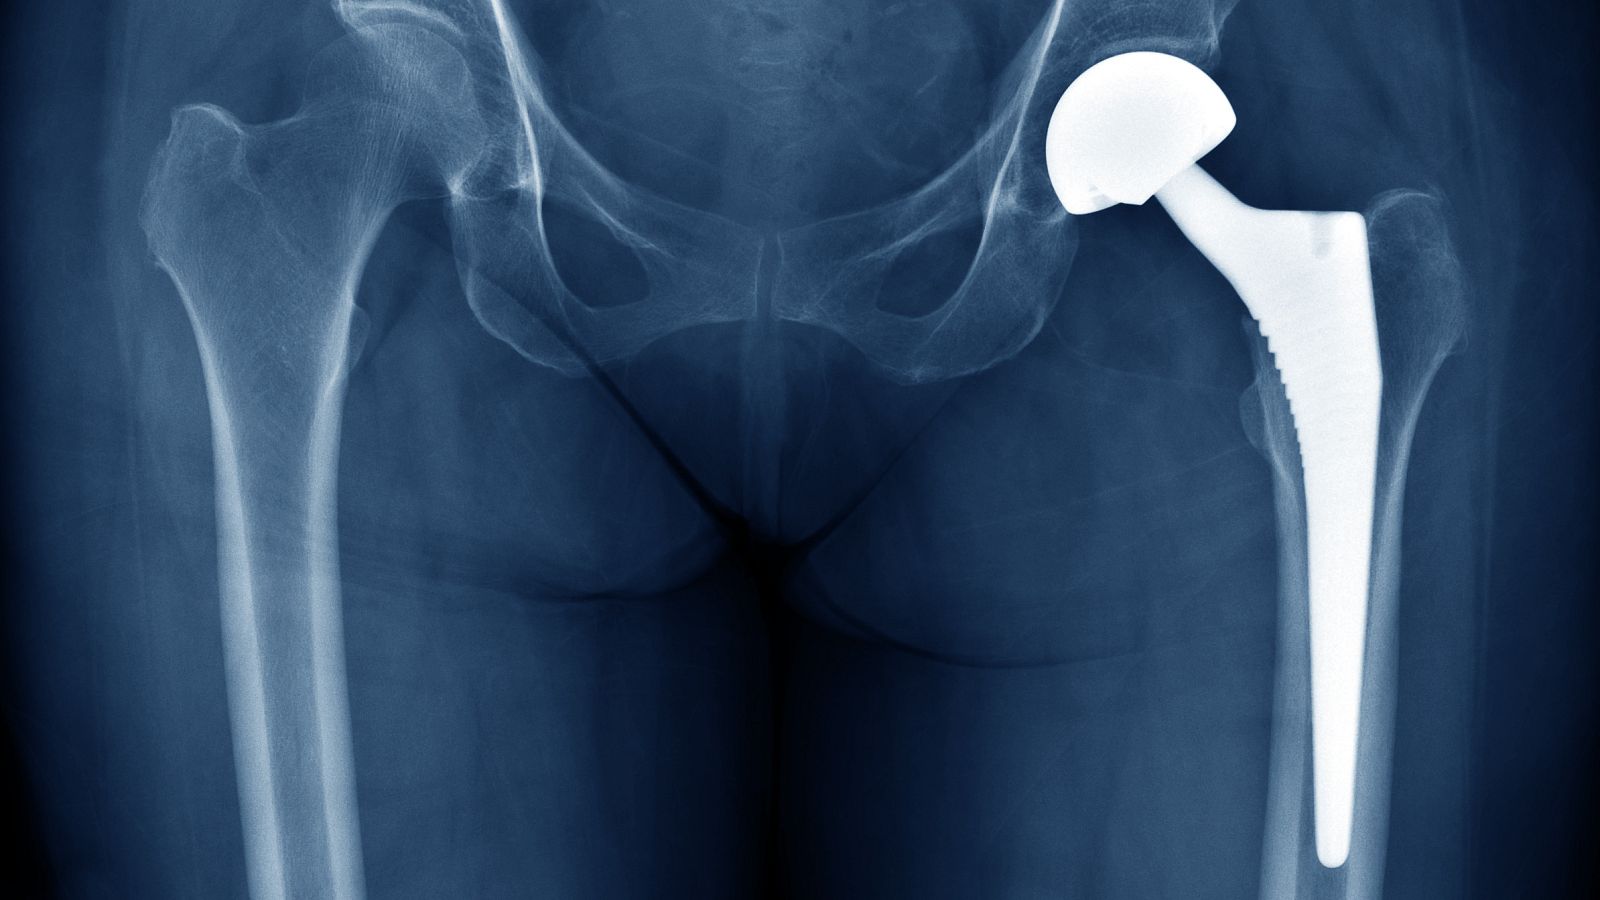

No recomendado para menores de 7 años La Audiencia Nacional está investigando a la farmacéutica estadounidense Johnson & Johnson por comercializar presuntamente prótesis de cadera defectuosas que han sido implantadas en varios países, entre ellos España, donde hay 1.471 afectados. Las pr